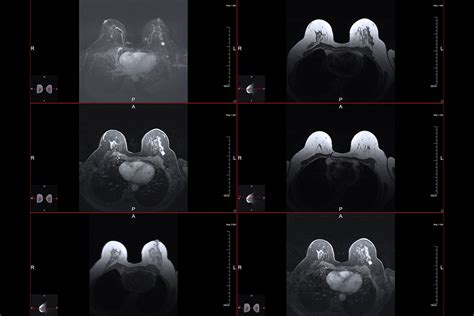

When it comes to advanced breast health diagnostics, an MRI of breasts stands out as one of the most sophisticated tools available to medical professionals. Unlike standard screening methods such as mammograms, which use X-rays, an MRI (Magnetic Resonance Imaging) utilizes strong magnetic fields and radio waves to create highly detailed, cross-sectional images of the breast tissue. This technology is particularly valuable because it can provide a different perspective on breast structure, often identifying abnormalities that might be obscured in denser tissue. For patients navigating a diagnosis or high-risk screening, understanding what this procedure entails is the first step toward feeling empowered and informed about their healthcare journey.

The experience of an MRI of breasts is unique compared to a mammogram. During the procedure, you will lie face down on a specialized platform that has openings for your breasts. This positioning is essential to allow the breast tissue to hang naturally and to ensure the most accurate imaging.

Once the MRI of breasts is complete, the images are sent to a radiologist who specializes in breast imaging. They will analyze the scans, looking for patterns of enhancement that suggest either benign or malignant tissue. It is important to remember that not every abnormality identified on an MRI requires surgery or a biopsy.